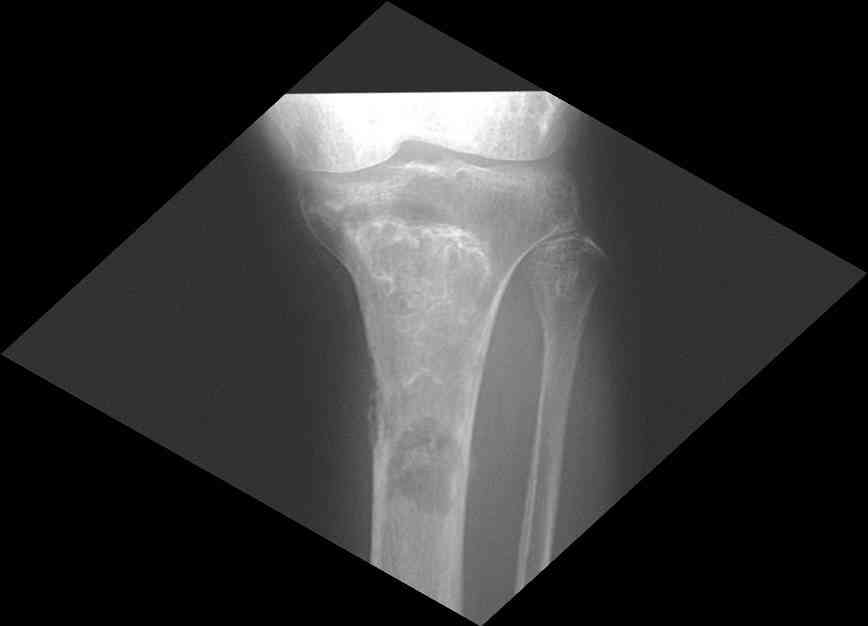

Изменения структуры костей у Вашего пациента больше похожи на полиоссальную форму фиброзной дисплазии или болезнь Педжета, возможены также инфаркты костного мозга б.берцовых костей. К сожалению, качество снимка не очень хорошее, непонятно, сохранен ли кортикальный слой б.берцовых костей по передней поверхности.

Для примера привожу случай из архива американской ассоциации рентгенологов (ACR) - развитие злокачественной фиброзной гистиоцитомы на левой б.берцовой кости у пациента с множественными инфарктами костного мозга (рис 4,5 - левая, рис 6 - правая)